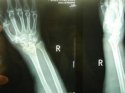

上一期草莓软件APP下载讲诉了患桡骨远端骨折的原因及其注意事项, 草莓视频入口仪品牌 草莓软件APP下载继续为您讲述桡骨骨折后如何更好的恢复。 1、俗话说伤筋动骨一百天,有钢板的在1年内每月到医院复

桡骨是人体前臂双骨之一,位于前臂外侧,大拇指一侧,分为一体和两端。是前臂长骨之一;蛙、蟾蜍等动物的桡骨与尺骨愈合成桡尺骨。 草莓视频入口仪厂家 草莓软件APP下载为您讲述桡骨引起的